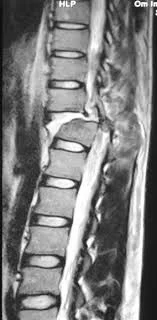

Η διάγνωση βασίζεται σε συνδυασμό κλινικής εξέτασης και σύγχρονης απεικόνισης, με κύρια εργαλεία την αξονική (CT) και τη μαγνητική τομογραφία (MRI).

• Αξονική τομογραφία (CT) – «εξέταση εκλογής» για τον οστικό τραυματισμό: κατάγματα, βαθμός κατακερματισμού οστικών τεμαχίων, συμμετρία οπίσθιων στοιχείων.

• Μαγνητική τομογραφία (MRI) – δείχνει βλάβες στον νωτιαίο μυελό, τους μεσοσπονδύλιους δίσκους, τους συνδέσμους και τυχόν αιματώματα/πίεση. STIR ακολουθίες βοηθούν να φανεί αν μια βλάβη είναι οξεία και αν έχουν ραγεί τα οπίσθια συνδεσμικά στοιχεία.

Η MRI είναι ιδιαίτερα σημαντική σε ασθενείς συμπτωματικούς με νευρολογικά ελλείμματα, για να διευκρινιστεί η ανάγκη και ο τύπος αποσυμπίεσης.